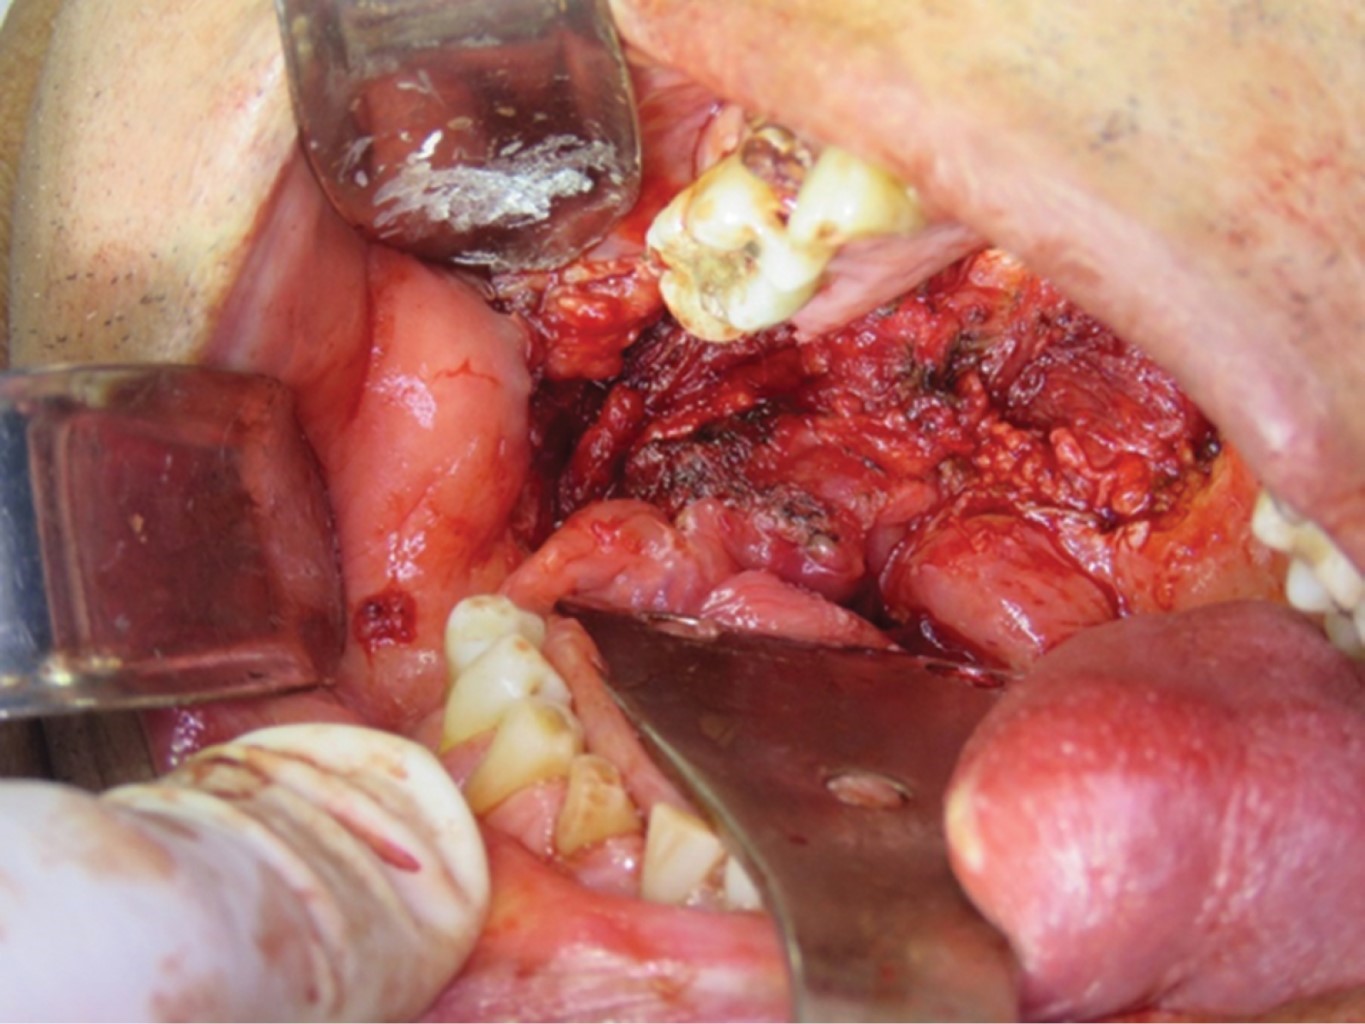

A la exploración clínica se aprecia adecuada simetría facial, perfil recto, sin limitación a la apertura oral. Sin adenomegalias cervicales. Intraoralmente se observa tumoración de 3 × 6 cm de dimensión, localizado en paladar blando que se proyecta a mucosa alveolar inferior retromolar y se extiende a pilar anterior amigdalino del lado derecho, indurado y no dolorosa a la palpación, de coloración violácea, con sangrado al menor estímulo, presenta área de necrosis tisular en el extremo derecho de la tumoración (Figura 1). El resto de la mucosa bien hidratada de color y consistencia normal, anodoncia parcial, prótesis fija metálica anterosuperior desajustada, mala higiene.

La intervención quirúrgica se basó en la toma de biopsia excisional, la cual se llevó a cabo bajo anestesia general balanceada. Se envía la muestra a examen histopatológico, se reporta tumor morfológicamente compatible con carcinoma de células acinares de glándula salival de tamaño 4 × 3 × 2 cm, márgenes y lecho quirúrgico libre de lesión (Figuras 4 y 5).

Figura 1

Figura 4